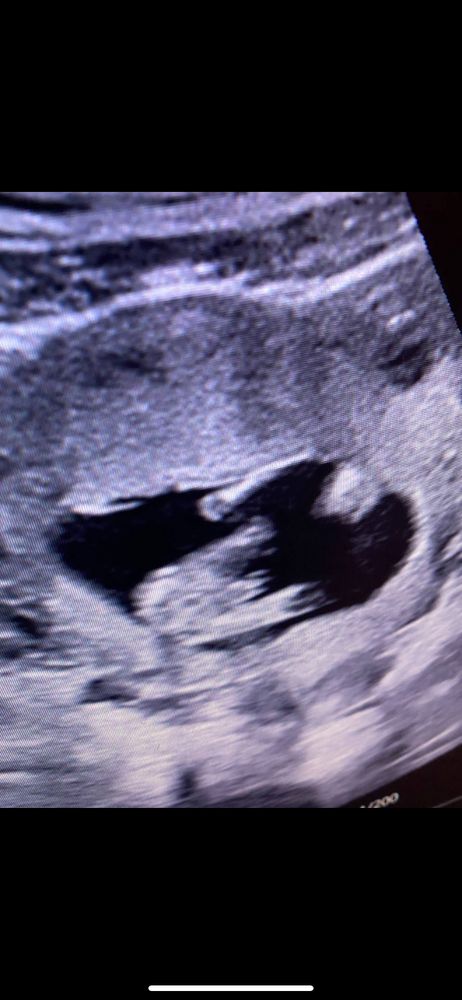

Ошибаются часто с девочкой, когда не видно, а тут имхо все понятно 😅

Ну тут ошибки быть не может, мальчишка

У нас такое же точно фото) мальчика ждём💙

У вас мальчик.))

Тут вроде четко видно, что мальчик. Единственное исключение, если это попувина торчит, но чаще всего ее легко распознать по кровотокам и думаю узист бы это сразу увидел.))

Мне кажется,тут отчетливо видно,что мальчик)

на втором скрининге скажут точно… хотя мне на первом в 12-13 нед уже точно всех мальчиков предсказали)) Тем не менее - могут ли ошибиться на 15нед, маловероятно, но могут, на 20 нед на хорошем оборудовании не могут.

Ну тут прям вряд ли это девочкины причиндалы), я бы на мальчика думала.

В 15 недель может быть ошибка) у меня подруга даже гендер пати с шарами и всеми делами устраивала, в 16 недель опытный врач мальчика определила и они сами видели стручок. В 20 недель на скрининге сказали девочка, родилась девочка. Дело было в том году, аппаратура хорошая, врач опытный)) в 15 недель ещё может половой бугорок быть видно

Зина, но все таки половой бугорок может быть видно на другом ракурсе, снизу сразу будет понятно кто там, ошибка еще может произойти, если у девочки большие половые губы, либо наоборот - у мальчика не то чтобы пенис не большой, он может прилипнуть , и его просто не видно, а по одним кокушкам тоже не поймешь, вдруг губы такие 🤪 нюансов много😂